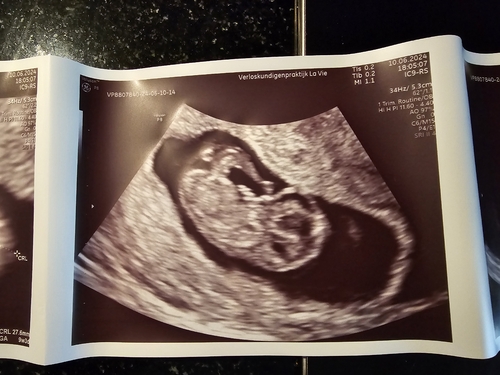

Net de termijnecho gehad en mijn uitgerekende datum is ook 2 januari 馃グ zo leuk om dit weer mee te mogen maken, dat je al zo goed alles kunt zien.